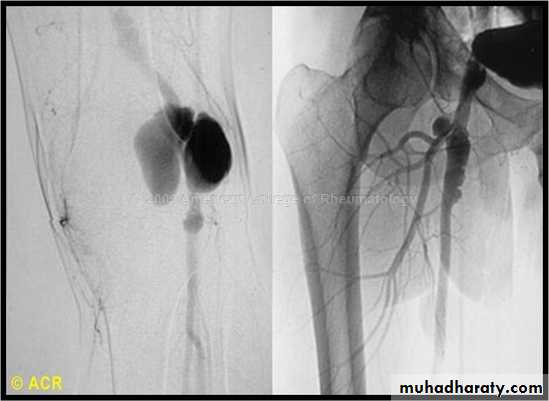

Femoral aneurysm

Popliteal aneurysm